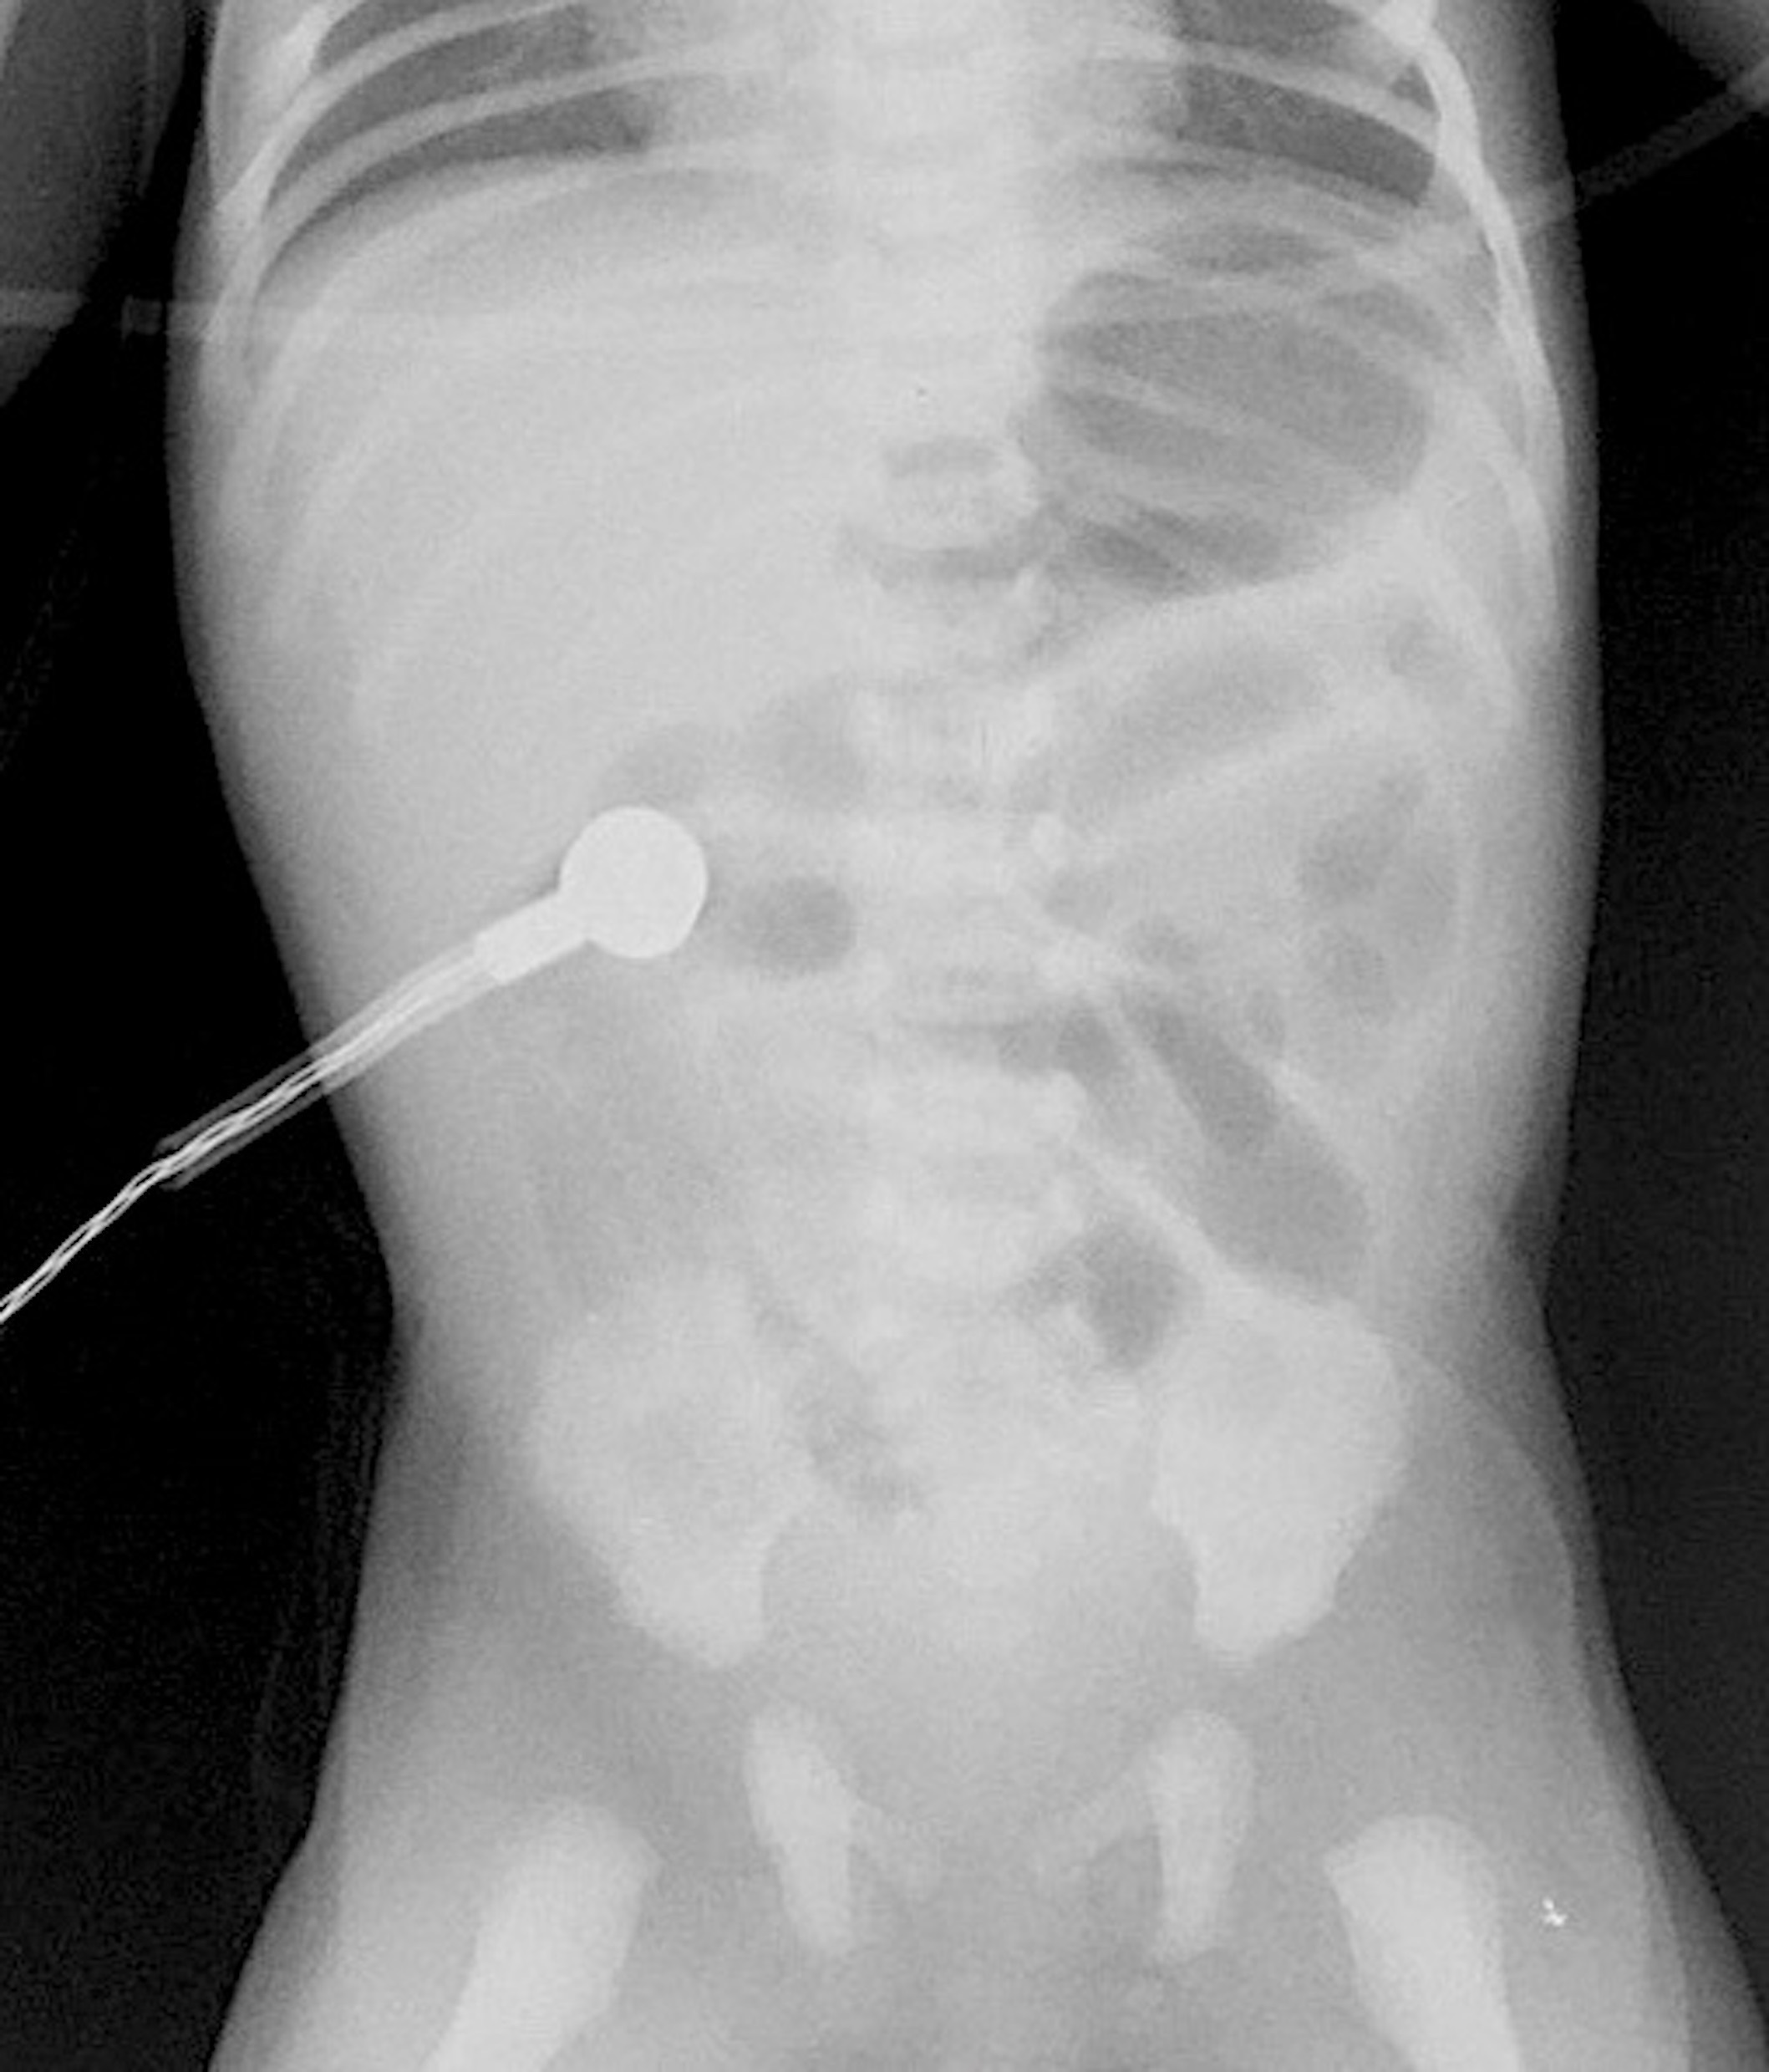

A term male baby, with a birth weight of 3.2kg, was born by normal vaginal delivery to a gravida-3 mother. Feeds were started and the baby was well till about 30 hours of life when the child developed vomiting which was initially nonbilious, and later turned bilious in nature. The child was reviewed by a Pediatric Surgeon at another center, where the child was admitted and started on IV antibiotics and IV fluids. Upper GI contrast study was done which showed dilated proximal small bowel loops and absence of distal bowel gas. The patient was referred to our center; on arrival, the patient’s heart rate was 140 beats per minute, and respiratory rate of 42 breaths per minute. Oxygen saturation was 97% on ambient air and nasogastric output was bilious. The abdomen was distended, soft, the hernial sites were normal, and the anal opening was normally located. On auscultation, bowel sounds were exaggerated. A supine radiograph of the abdomen showed dilated central small bowel loops but no air shadows in the pelvis (Fig. 1). Ultrasound of the abdomen showed dilated gas-filled bowel loops and Doppler showed normal orientation of superior mesenteric vessels. Laboratory examination showed a normal CBC and serum electrolytes.

Our patient developed features of intestinal obstruction on the second day of life, though the baby passed meconium spontaneously on the first day of life and tolerated breastfeeding initially, thus minimizing the possibility of congenital causes of neonatal intestinal obstruction. The abdominal radiograph showed dilated central small bowel loops but the absence of gas shadows in the pelvis indicating a small bowel obstruction. The malrotation was also ruled out in our patient based on history, x-ray, and doppler findings.

Abdominal radiograph showing dilated small bowel loops and absence of gas shadows in the pelvis.